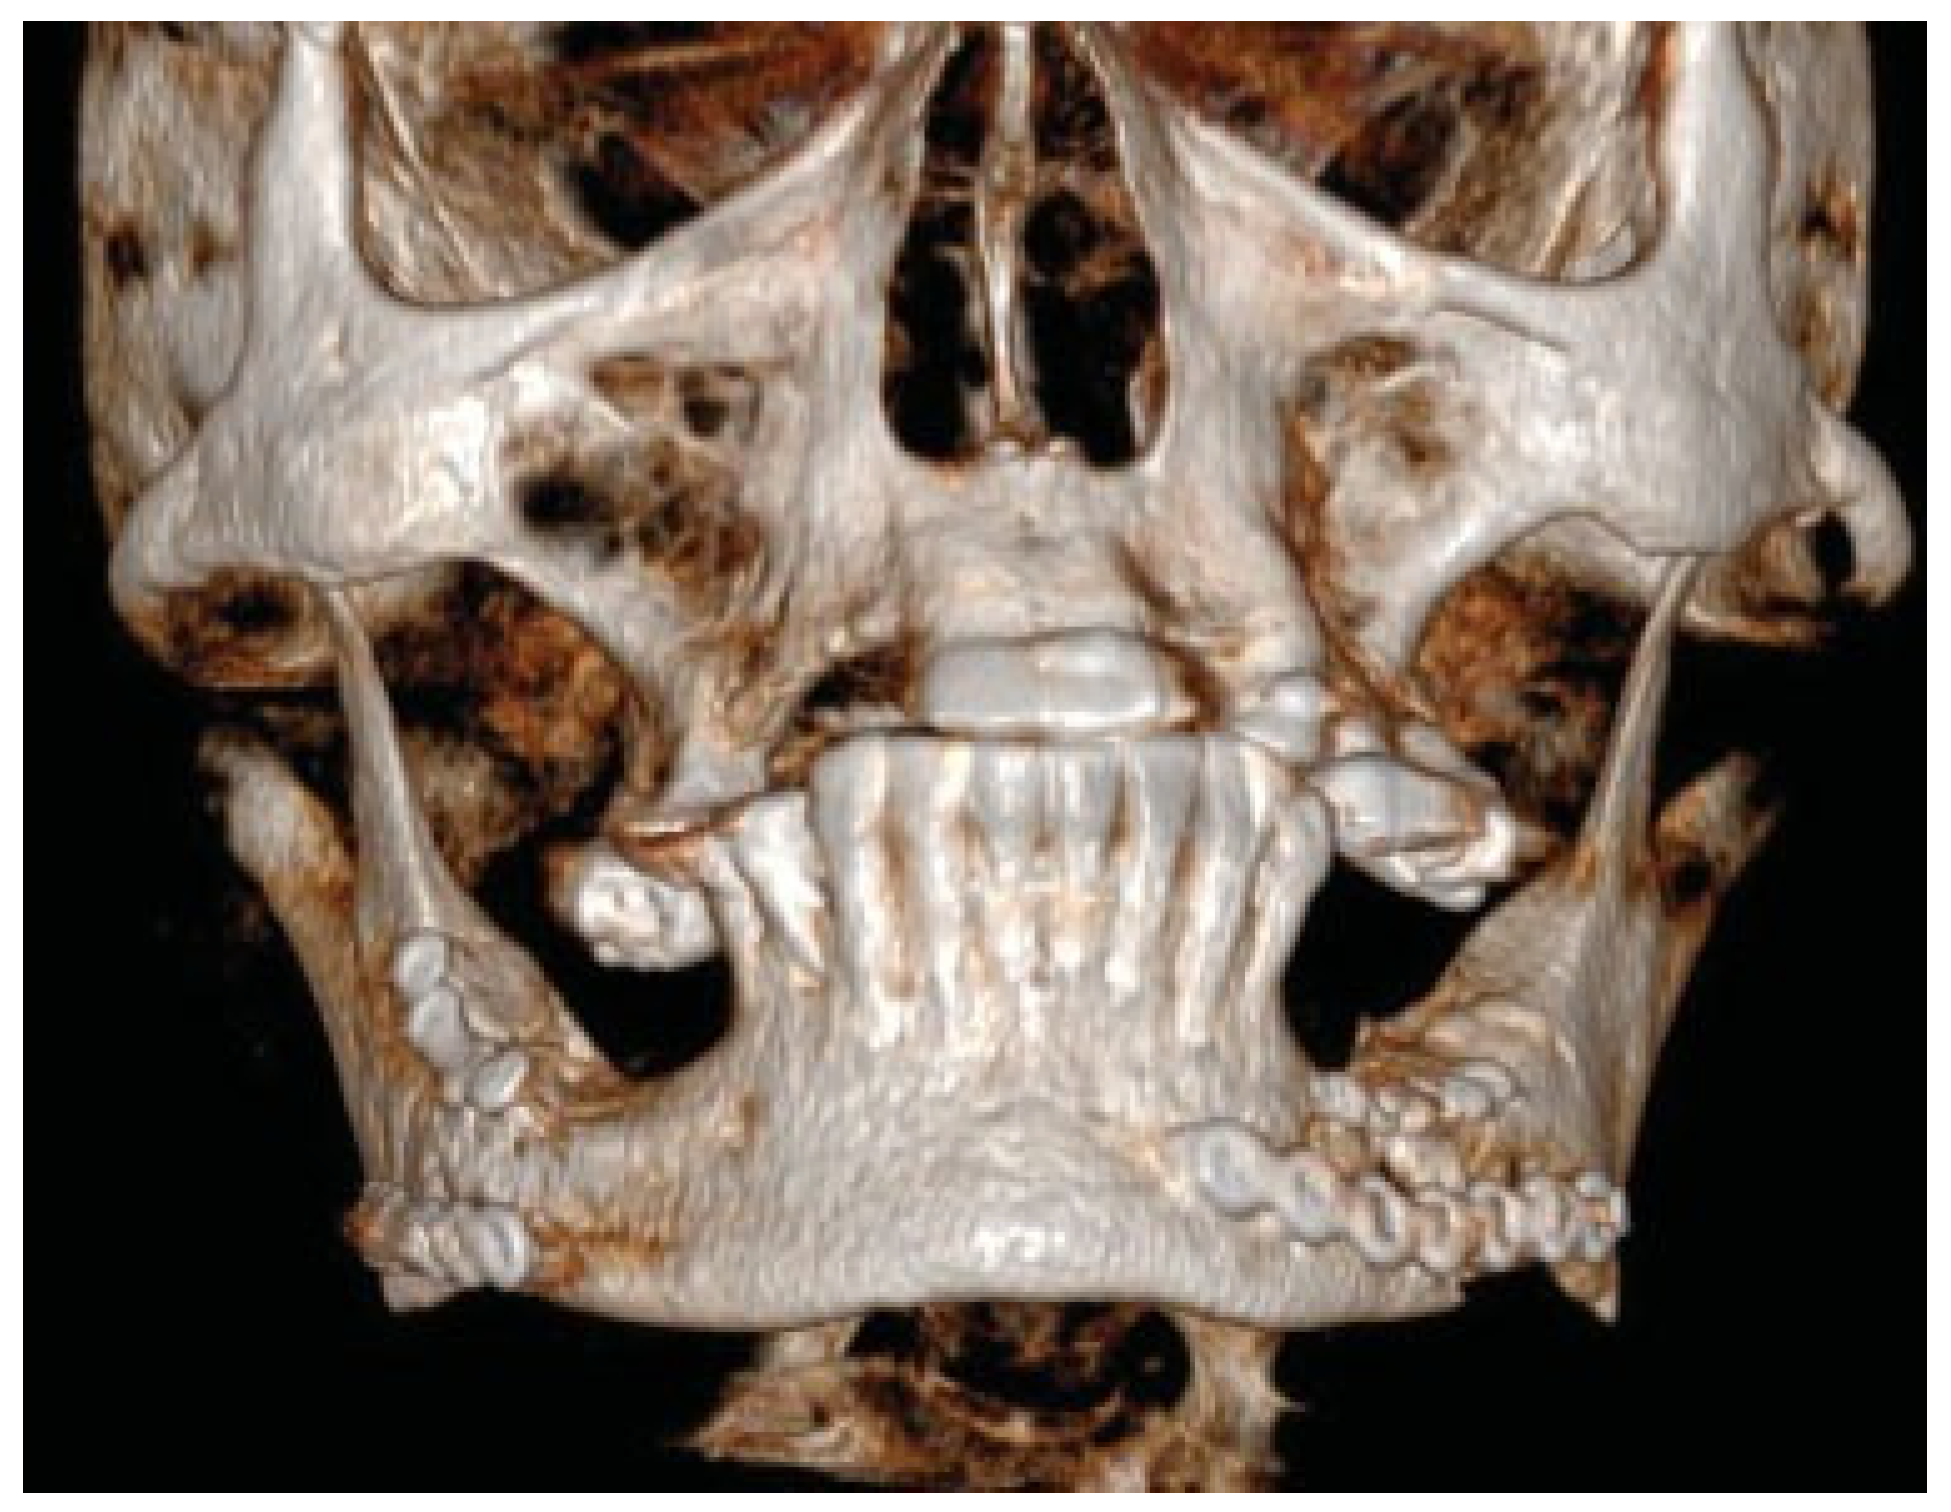

Figure 3.

Patient developed infections with oral mucosal fistulas in the fracture areas and an open bite. CBCT displays obvious anterior rotation of proximal segments and posterior rotation of the dentate part of mandible. Considerable muscle action creates new dislocation and is not counteracted by the inadequate osteosynthesis of the fractures.